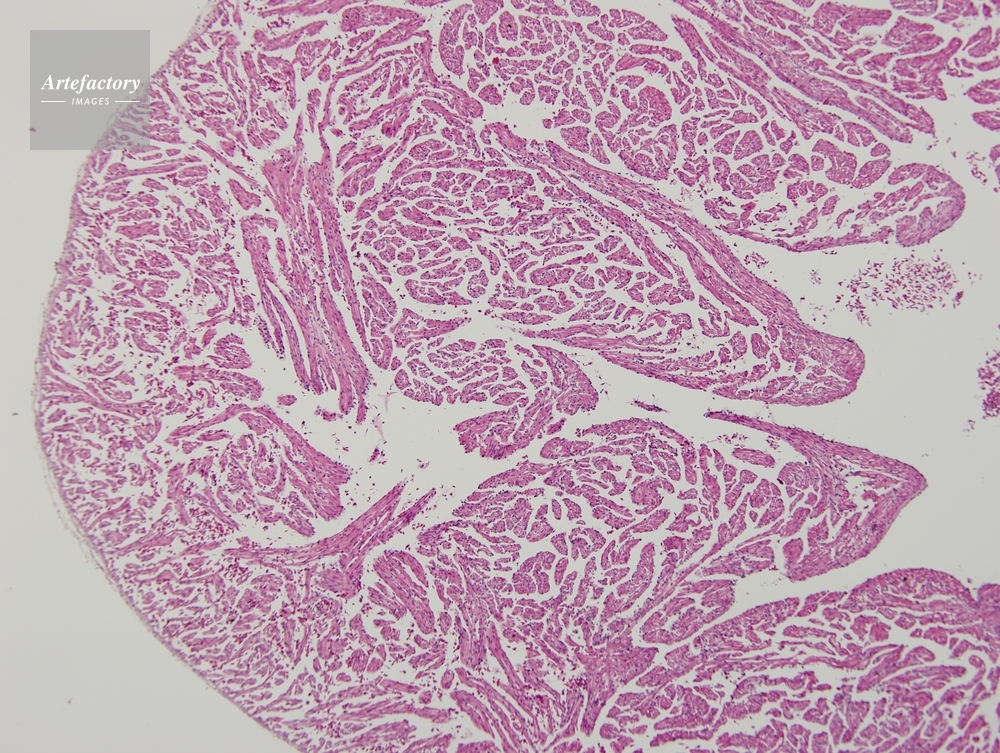

| 作品タイトル | ウシガエル,心臓 | モデルリリース | なし | |

| 作家 | OLYMPUS CORPORATION Technolab | プロパティリリース | なし | |